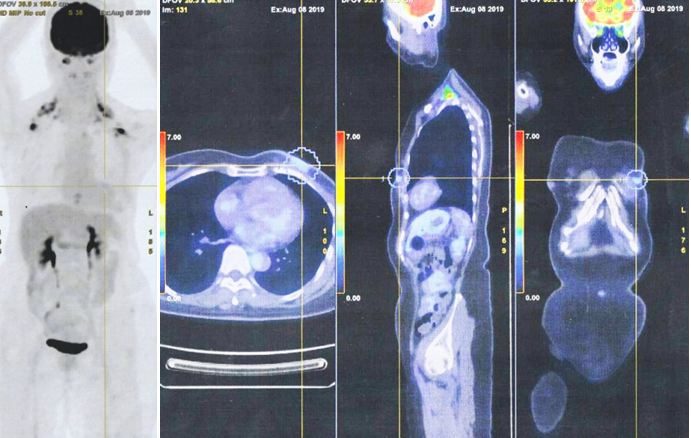

2. Pada tanggal 8 Agustus 2019, saya berkonsultasi dengan dokter spesialis onkologi di sebuah rumah sakit swasta di Kuala Lumpur. Pemindaian PET dilakukan. Hasilnya menunjukkan:

• Serapan FDG derajat rendah terlihat pada perubahan inflamasi pascaoperasi pada dinding dada anterior kiri. Tidak ada nodus hipermetabolik atau metastasis jauh.

Kemudian pemindaian PET menunjukkan “perubahan inflamasi” di dinding dada tetapi tidak ada metastasis. Dari sudut pandang medis, Lucy perlu menjalani setidaknya 6 siklus kemoterapi. Itu protokol standar.